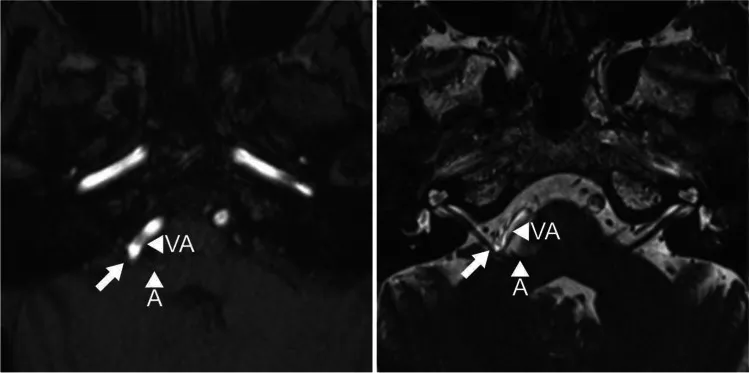

MRI发现小脑前下动脉与椎动脉明确压迫出脑干区的面神经(图1)。

确实,术中见粗大椎动脉严重推挤面神经。椎动脉将小脑前下动脉推向面神经,形成“夹心”式双重压迫。

因此,创建了一条Gortex吊带,将血管拉向侧面和后方,远离面神经根出口区(REZ)。在放置吊带的区域分离椎动脉时,发现了一条微小的穿支(图2C)。